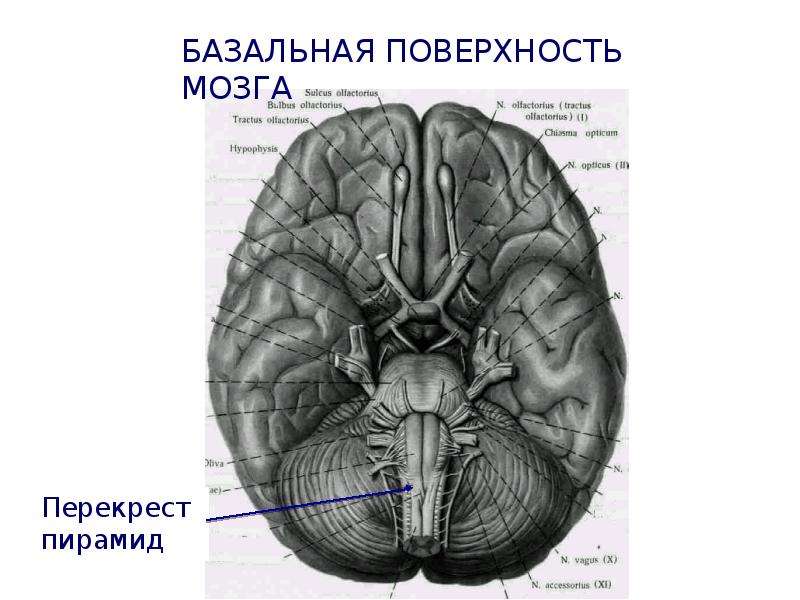

Анатомические снимки верхнелатеральной поверхности головного мозга